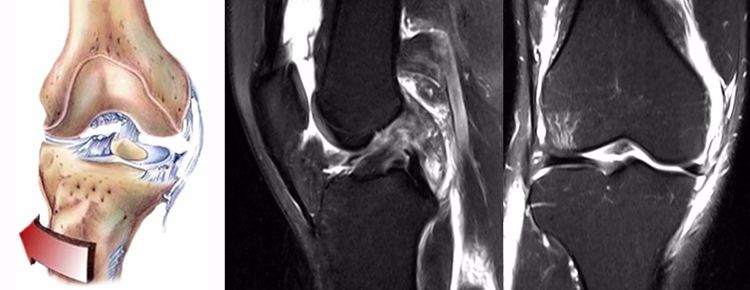

ACL损伤的MRI分级——

Grade1:韧带内损伤,无长度改变。

Grade2:韧带内损伤并长度延长。

Grade3:完全性韧带撕裂。

Grade1、2级为韧带的部分损伤,Grade3级为韧带的完全断裂。